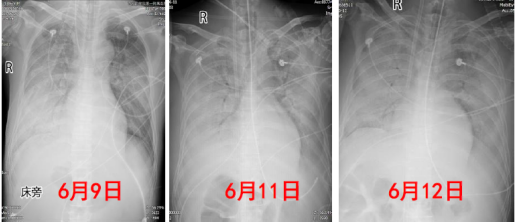

复查床旁胸部X线片可见患者心脏逐渐增大,肺部病变无明显好转(图3)

图片

3  建立ECMO前后患者胸部X线片变化情况